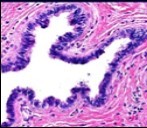

Figure 7.Cutaneous ciliated cyst with papillary structures, a coating of ciliated columnar epithelium supported by a connective tissue framework (15).

Cutaneous ciliated cyst is layered with a singular layer of ciliated epithelial cells which are chiefly constituted by cuboidal to columnar epithelium, traversed by partially configured fibrous tissue septa with an admixture of randomly dispersed, intraluminal papillary projections akin to those cogitated in the fallopian tube. Superimposed epithelium is inundated with well vascularized, parallel bundles of collagen although smooth muscle is absent 7, 8.

Alternatively, cutaneous ciliated cyst can be lined by non ciliated cuboidal or columnar epithelium with intermingled intercalated, dark or round peg cells. Foci of squamous metaplasia can be occasionally exemplified in the adherent epithelium whereas mucinous cells or apocrine-like features are exceptional 6, 8. Figure 1, Figure 2, Figure 3, Figure 4, Figure 5, Figure 6, Figure 7, Figure 8, Figure 9, Figure 10, Figure 11, Figure 12. 11, 12, 13, 14, 15, 16, 17, 18, 19.